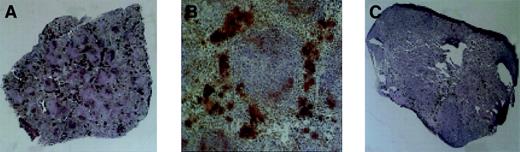

Megakaryopoiesis in the spleen, day 28 after transplantation.

Megakaryocytes stain dark as a consequence of histochemical staining for acetylcholinesterase. (A) Typical spleen of animal receiving Rholow stem cells. (B) A cluster of megakaryocytes in the perifollicular space after Rholow transplantation. (C) Animals receiving the Rhohigh progenitor have almost no splenic megakaryocyte activity. Original magnification A, × 20; B, × 100; and C, × 20.

Acetylcholinesterase staining was used to accentuate splenic megakaryocytopoiesis (Figure 5). The splenic red pulp had prominent staining of trapped platelets within the sinusoids when the platelet count was more than 200 000, at the earliest and latest time points. There was no change in size of the day-7 posttransplantation spleens in animals 7 days after receiving a transplant of Rholow stem cells, although there were a few small colonies of hematopoietic cells evident by microscopy. Clusters of megakaryocytes consisting of between 3 and 10 cells appeared 14 days following transplantation of Rholow stem cells and increased in number through day 28 (Figure 5A). The megakaryocyte clusters tended to form in the subcapsular and perifollicular areas within the red pulp and occurred alone, or in association with erythroid progenitors (Figure 5B). The spleens of the Rhohigh progenitors increased in size and cellularity 7 days after transplantation, with confluent macroscopic nodules clearly apparent on the splenic surface. In spite of this early, robust hematopoietic activity, almost no megakaryopoiesis was observed in the spleens of animals receiving the Rhohigh progenitors until approximately day 28 (Figure 5C). A gradual increase in splenic megakaryopoiesis occurred over the next 2 weeks, with colonies similar to those seen in animals receiving the Rholow stem cells 2 weeks earlier.